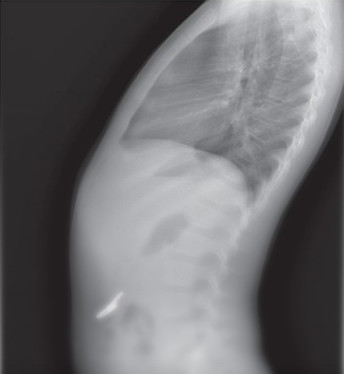

Шестилетний ребенок проглотил ключ | Фото: Jam Press

Несмотря на отсутствие физических симптомов, в приемном отделении был проведен рентген, который показал инородное тело в животе. Поскольку ключ не вызвал осложнений, медики решили не проводить операцию, а ограничиться наблюдением.

Специалисты регулярно делали рентген, чтобы отследить перемещение объекта. Через 48 часов снимки показали, что ключ уже добрался до кишечника.